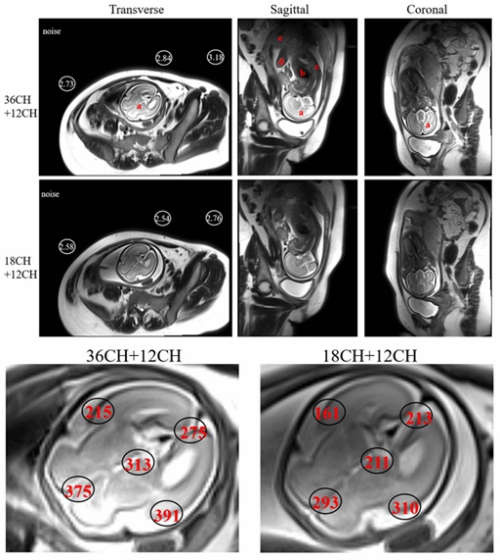

磁共振胎儿成像可发现复杂先天性疾病,尤其对神经发育异常和心血管疾病诊断有不可替代的价值。现有磁共振技术在成像速度和图像信噪比方面对于胎儿成像有较大的局限性。团队基于高灵敏电子设计了大范围、高密度多通道新型表面柔性线圈,与商用的线圈对比,设计的线圈的图像信噪比提高可达40%左右,更多的线圈单元可以显著提高成像速度,成功实现了清晰的胎儿大脑(2倍加速)和心脏电影(4倍加速)成像。相关成果发表在IEEE Transactions on Medical Imaging,第一作者为陈巧燕,通讯作者为郑海荣、李烨。

图2 设计的36通道线圈(结合12通道脊椎线圈)与商用的18通道线圈(结合12通道脊椎线圈)的胎儿大脑(2倍加速)成像结果对比,36通道线圈可以明显提高图像信噪比,高达40%左右。